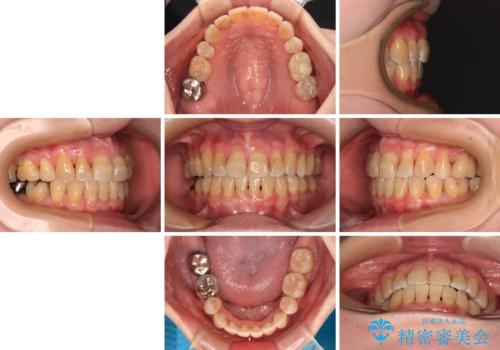

- 矯正装置

- クリアブラケット

- 治療期間

- 1年7ヶ月

- 治療計画

- 口元の突出感を気にして来院された患者様です。

上下前歯が著しく前突している状態であったので、上下左右の小臼歯4本を抜歯し、ワイヤー装置にて矯正治療を行うこととしました。

上顎左側は第二小臼歯に大きなむし歯があったため、通常は第一小臼歯を抜歯するところ、イレギュラーに第二小臼歯を抜歯することとしました。

抜歯する第二小臼歯の後方の歯は神経近くにまで及ぶむし歯があったため、事前に処置をしておき、矯正治療後にオールセラミッククラウンにて補綴治療を行うこととしました。

第二小臼歯抜歯はイレギュラーな治療となるため、アンカースクリューを補助的に使用して、スムーズに治療を行えるように工夫をしました。